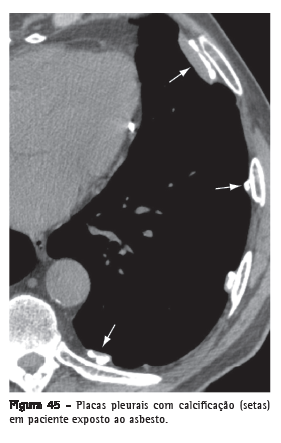

Placa pleuralEspessamento pleural focal, por vezes com calcificações, de espessura variável e com extensão de até 5 cm (Figura 45).(68) Usualmente ocorre

na superfície pleural parietal subcostal ou na pleura diafragmática.

Quando múltiplas e bilaterais, são quase sempre decorrentes de exposição ao asbesto.(69,70)